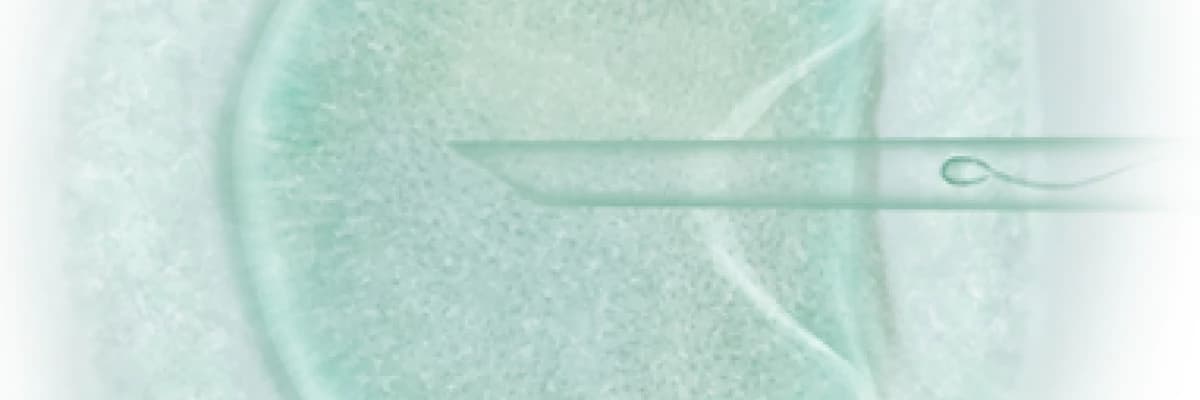

Tüp bebek yöntemiyle ilk bebeğin doğumundan bu yana neredeyse 30 yıl geçmiş ve kullanılan yöntem ve teknolojilerde o zamandan bu zamana inanılmaz gelişme göstermiştir. Dolayısıyla; üreme problemleri ile ilgili tüp bebek ya da aşılama tedavilerine yönelik yaptığınız araştırmalarda, girdiğinizi web sitelerinde tıbbi tedavinize yönelik detaylı bilgileri bulabilirsiniz. Ancak bu süreçte yaşayabileceğiniz psikolojik sıkıntılar ve bunlarla nasıl baş edebileceğinize dair bilgiler oldukça azdır.

Doğurgan Zihin Doğurgan Beden Metodu üreme problemleri ile ilgili uygulanan tıbbi tedavilerin başarı oranını destekleyen, zihin-beden etkileşimini kabul eden psikolojik müdahalelerin kullanıldığı etkili bir yaklaşımdır.